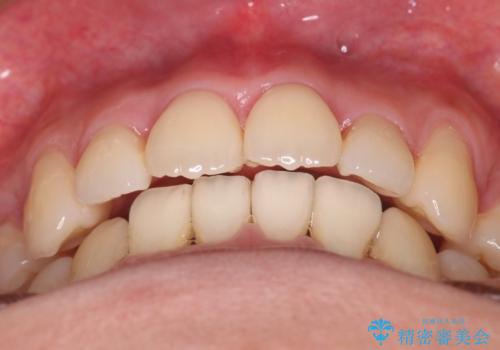

主訴である前歯のデコボコが改善され、噛みあわせも綺麗になりました。

歯肉退縮もなく、予定通りに治療を終えることができ良かったです。